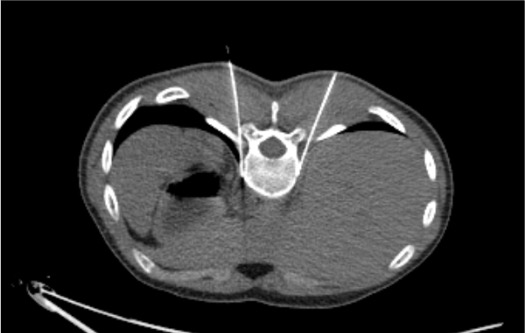

Paravertebral Target Space

- Target: T11–T12 paravertebral fat space, anteromedial to the rib head, anterior to the vertebral body

- Nerves run in a groove between the vertebral body and the rib head at this level

- Needle tip should be in the paravertebral fat anterior to the rib head / costovertebral junction

- Diaphragmatic crus runs just caudal to this level; the splanchnic nerves cross under the crus to reach the celiac plexus

- Pleural reflection is immediately adjacent — monitor for apical spread of contrast or ice ball toward pleural space